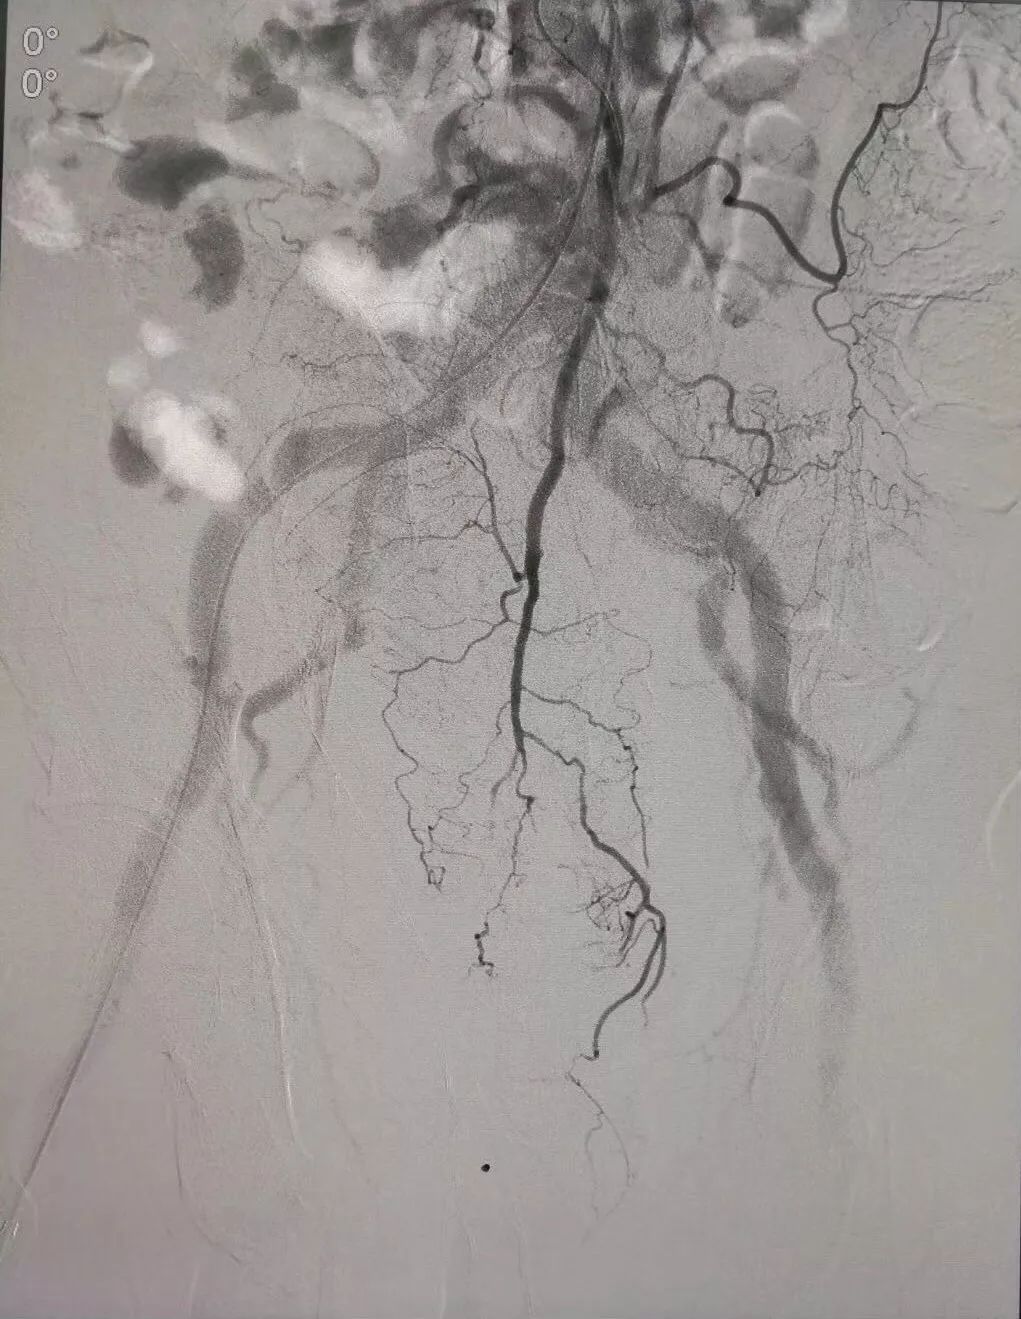

(术前DSA造影提示肠系下动脉增粗、增多、絮乱,临床表现为便血,系破裂出血)

(介入栓塞术后造影提示肠系膜下直肠动脉走向规则,清晰,术后出血症状停止,血压明显稳定)